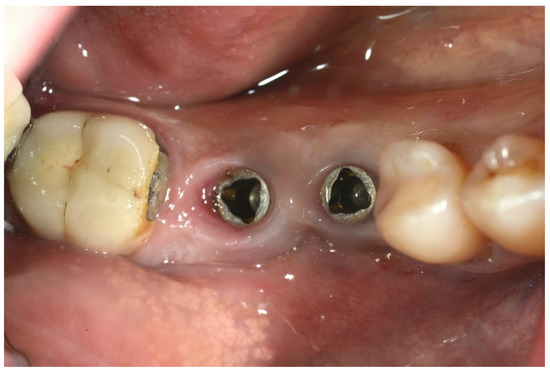

Peri-Implantitis: Application of a Protocol for the Regeneration of Deep Osseous Defects. A Retrospective Case Series

2. Materials and Methods